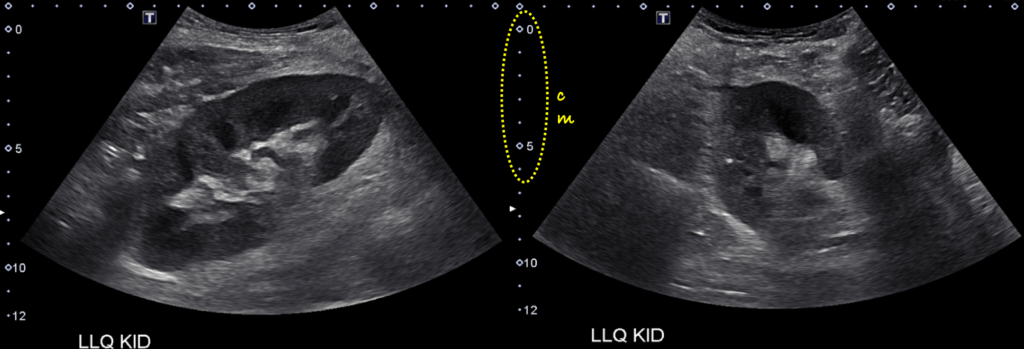

Normal Kidney Transplant. The image demonstrates a normal left lower quadrant renal allograft. Transplanted kidney essentially looks the same as native kidney on a sonogram except for its superficial location (note the depth from skin surface on the scale) and that no associated liver or spleen will be seen in the image.

Normal Kidney Transplant. Normal allograft with slightly distended pelvicalyceal system (indicated with asterisks). Note that the collecting system of a well-functioning transplanted kidney is often slightly dilated, likely because of a combination of an increased volume of urine produced (i.e. acting as the sole kidney), loss of the ureter’s tonicity from denervation and altered anatomy of the ureterovesical junction due to surgery.